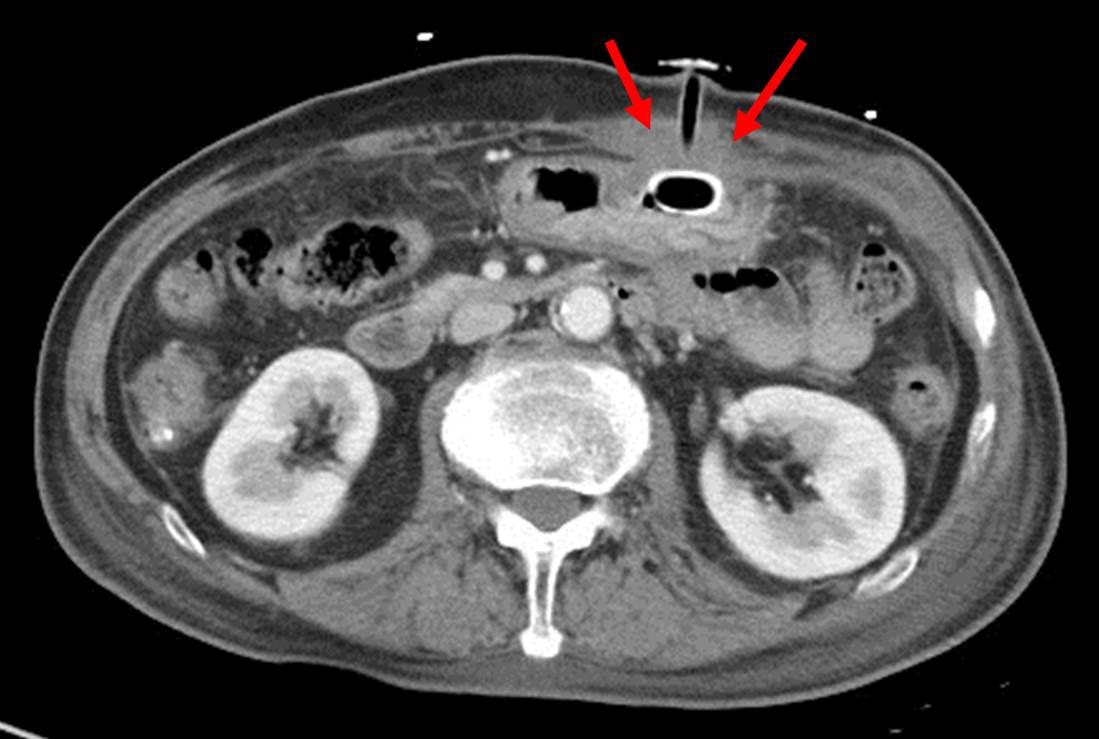

M/85. PEG tube insertion ÈÄ ½ÄÀÌ ÁøÇàÀÌ Àß µÇ¾ú´ø ºÐÀÔ´Ï´Ù. 6°³¿ù ÈÄ PEG tube change ÈÄ ½ÄÀÌ ÁøÇàÀÌ µÇÁö ¾Ê¾Æ CT¸¦ Âï¾ú°í colonic fistula°¡ È®ÀεǾú½À´Ï´Ù. PEG tube removal ÈÄ Neovil°ú Veriplast·Î fistula¿¡ ´ëÇÑ Ä¡·á¸¦ ÇÏ¿´½À´Ï´Ù. PEG »ðÀÔ ½Ã gastrocolocutaneous fistula°¡ »ý°å´Ù°¡ tube change ÀÌÈÄ¿¡ tube ³¡ÀÌ ´ëÀåÀ¸·Î µé¾î°¡¼­ ¹ß°ßµÈ Áõ·ÊÀÔ´Ï´Ù.